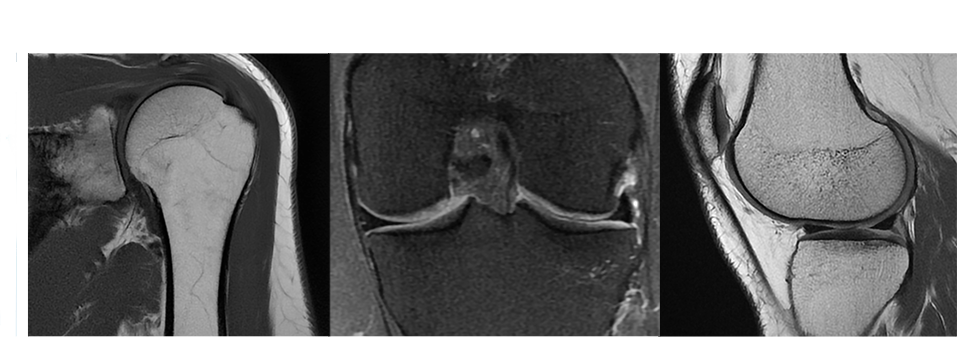

This extensive library of musculoskeletal imaging techniques enables you to image bone, joint and soft tissue with remarkable tissue contrast.

OrthoWorks also includes 3D volumetric Cube with proton-density, combined with ASPIR, which enables improved fat suppression uniformity, which is routinely done as three separate 2D scans. With one 3D acquistion and multi planar reformats, Cubes may replace individual 2D scans.PaedWorks